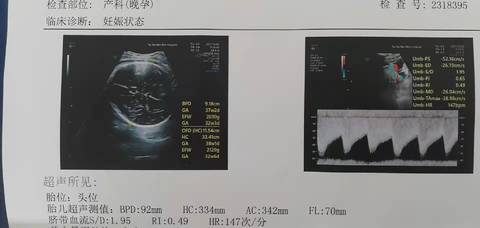

表示查出来的数值代表不同的孕周,如头围92代表相对应的孕周是37+2。